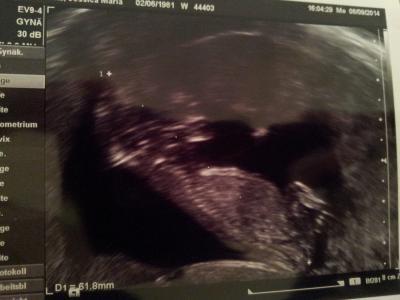

Babylein ist 6cm Ssl, zeitgerecht und ohne Auffälligkeiten :) Soll mich aber trotzdem in der Uniklinik vorstellen zur weiteren Betreuung da er noch nie eine Patientin mit meiner Krankheit hatte. Krümel hst getobt wie verrückt als würde es ihm jetzt besser gehen. Bin erleichtert. Lg Jessy

Bild zu so zurück vom Fa - Forum für März - Mamis